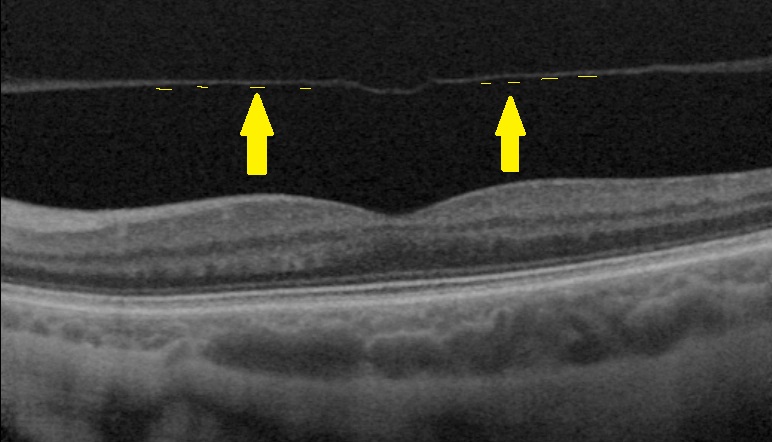

Chorio-rétinopathie séreuse centrale

La CRSC est une pathologie de la choroïde, tissu de soutien très vascularisé de la rétine, qui se traduit par la survenue de bulles de liquide sous la rétine alimentées par des points de fuite au niveau de l’épithélium pigmenté de la rétine.